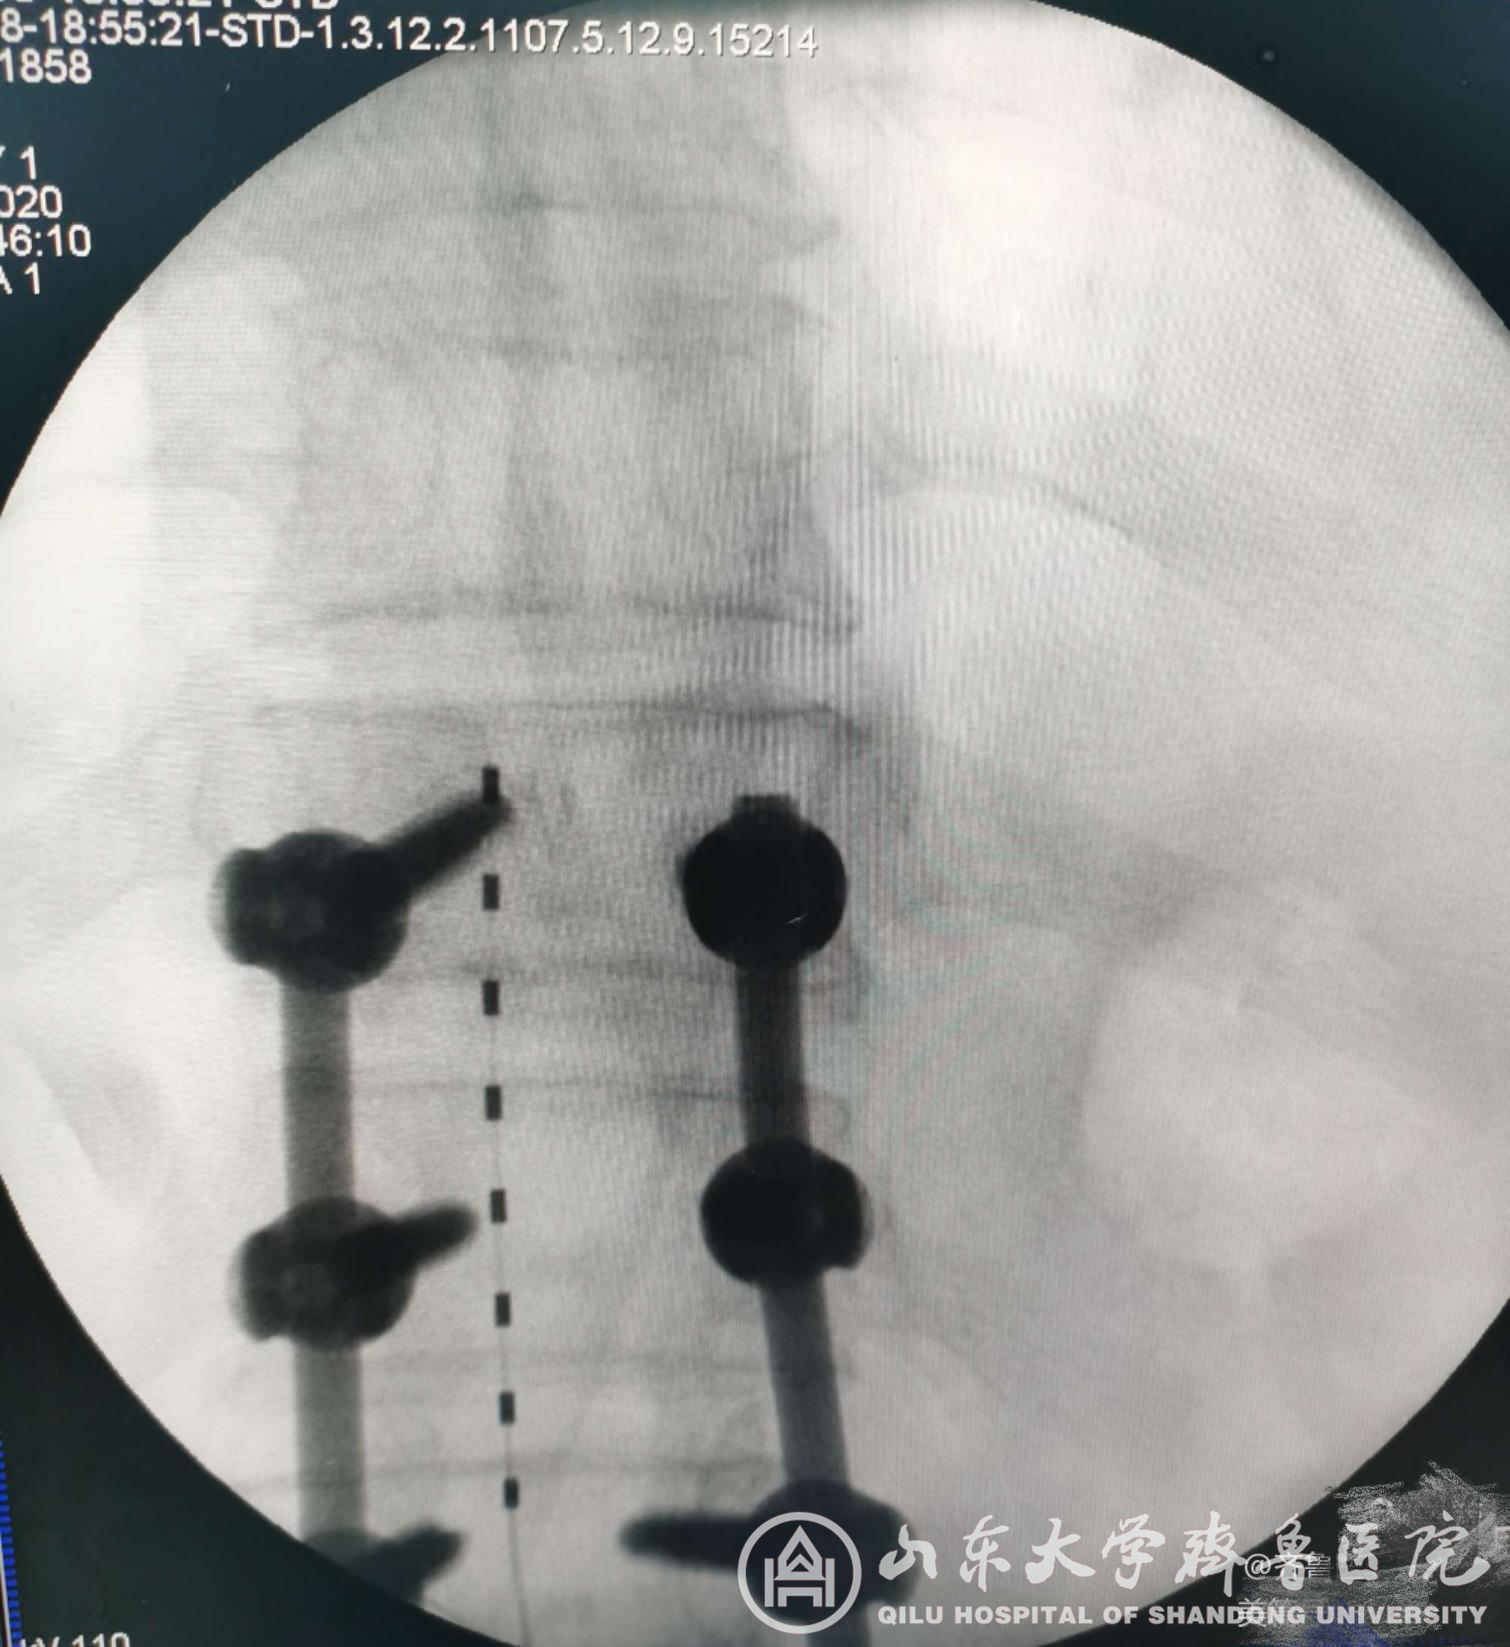

图4.腰椎术后顽固性疼痛患者术后X线检查电极位置良好